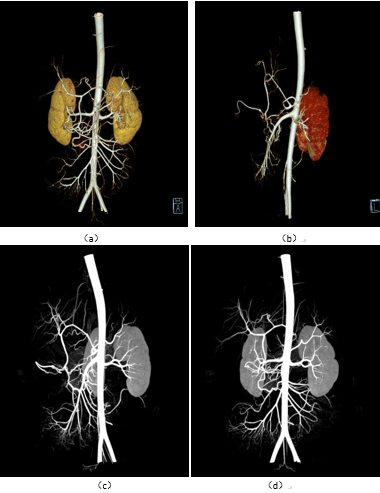

图3:肝动脉显影(VRT/MIP)

6:肝动脉VRT